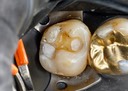

Mendel Sato #12 impression

Mendel Sato #12 prep